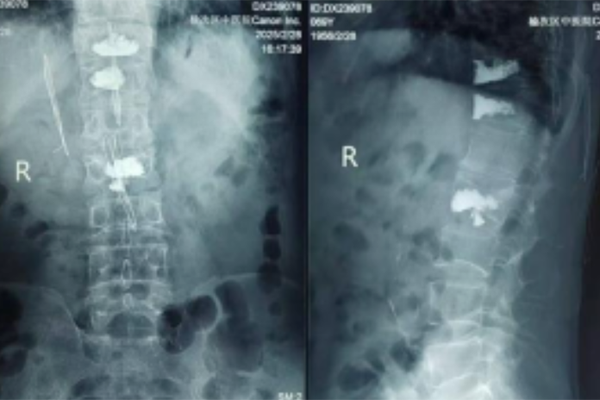

术后腰椎正侧位检查

术后患者恢复显著:6小时即可无痛翻身,24小时后进行康复行走训练,72小时康复出院。此次成功得益于该科“中医正骨固本+微创手术治标”的独特治疗体系。据了解,近三年已累计开展脊柱微创手术百余例,其中35%为高龄患者,40%实现三日出院。